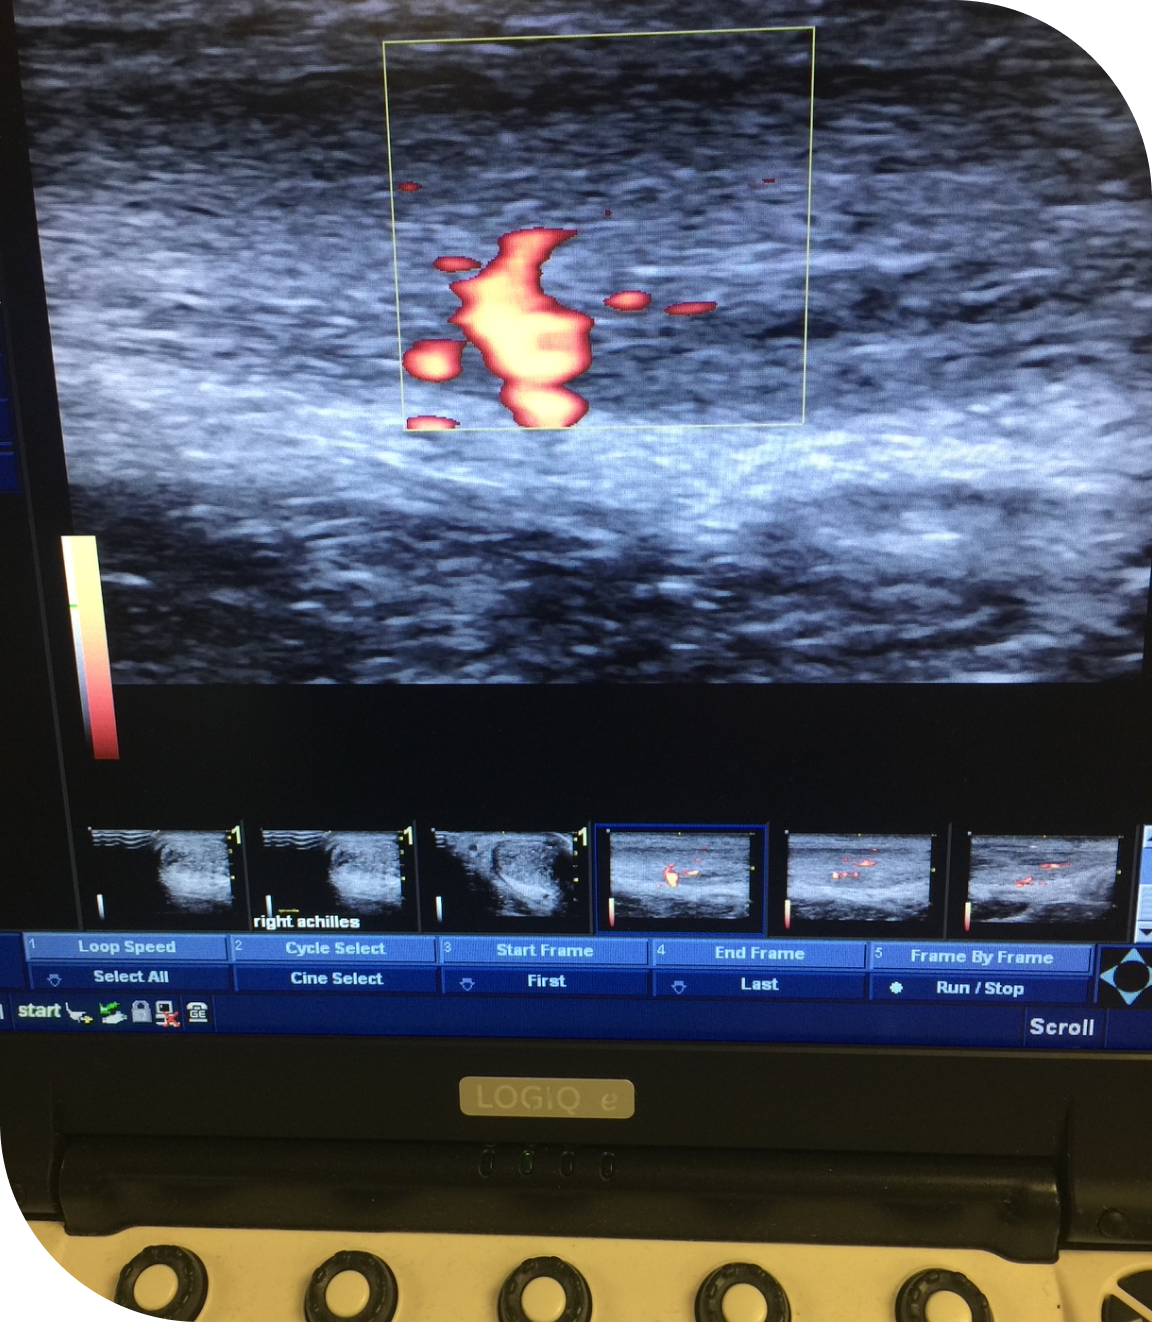

Dr. Clarke Holmes offers musculoskeletal ultrasound (MSK ultrasound) as part of his advanced diagnostic and

treatment services. This non-invasive imaging allows for

real-time evaluation of soft tissue injuries and joint conditions. MSK ultrasound is used to assess concerns including joint inflammation, ligament sprains and tears, muscle strains, bursitis, and tendon injuries like rotator cuff, tennis and golfer’s elbow or Achilles tendon/plantar fascia issues.

• Ankle and Foot (Achilles, posterior tibial and peroneal tendonitis; plantar fasciitis)